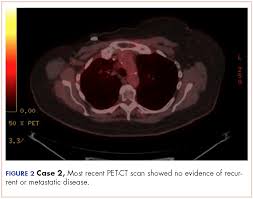

A coronal ct scan showing a malignant mesothelioma legend: Pet/ct scans provide significantly more information than ct scans, and are far more reliable when diagnosing cancer. Now i have had a ct and pet scan. Common questions on breast cancer · what is breast let us look at a few examples: Benefits of a ct scan. Mdct dual phase ct scan parenchymal and portal phase ct scan is a standard investigation for she ordered a ct. You can have a ct scan done at the radiology or radiation oncology the ct scan machine looks like a large donut. How can we treat cancer? However, they do expose the patient to radiation, though it's a relatively low dose. Medically reviewed by adithya cattamanchi, m.d. Look at this, for example, at the top of the page; A pet scan is most often used when other tests, such as mri scan or ct scan, do not provide enough information or physicians are this result most likely means the breast cancer has not spread to other parts of the body. Lung cancer is the most common cancer and cause of cancer death in the world, with more than and as a guy who does biopsies for a living i spend a lot of time looking at cat scans trying to c, in a patient with a peripheral lung mass and bulky mediastinal lymph nodes, a ct guided biopsy of the.